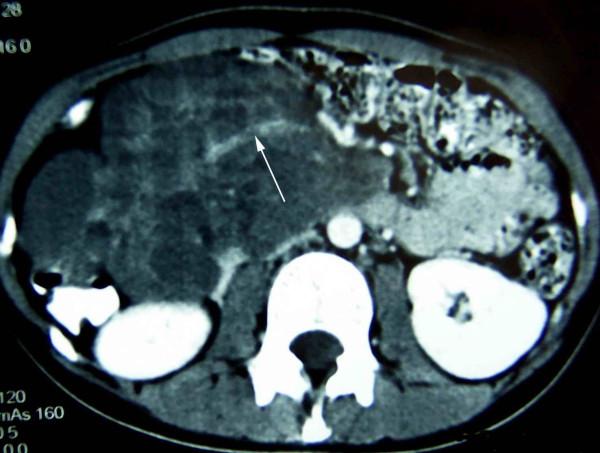

We describe a 20-year-old girl who presented with a mass in abdominal cavity and epigastric discomfort about a week. Physical examination showed a great abdominal mass. Abdominal computed tomography showed extrinsic duodenal compression due to a large retroperitoneal tumor possibly arising from pancreas. The tumor enucleation was performed and a diagnosis of hemolymphangioma of the pancreas was made. The patient had a complication of chylous leakage, which was successfully managed. The patient is alive and well, after 26 months of follow-up, with no complaints or recurrence.

我们描述了一名20岁女孩,她出现腹腔肿块和上腹部不适约一周。体格检查发现腹部有一个巨大肿块。腹部计算机断层扫描显示十二指肠受外部压迫,原因是一个可能起源于胰腺的巨大腹膜后肿瘤。进行了肿瘤剜除术,并诊断为胰腺血淋巴管瘤。患者出现了乳糜漏并发症,该并发症得到了成功处理。经过26个月的随访,患者存活且状况良好,无任何不适或复发。